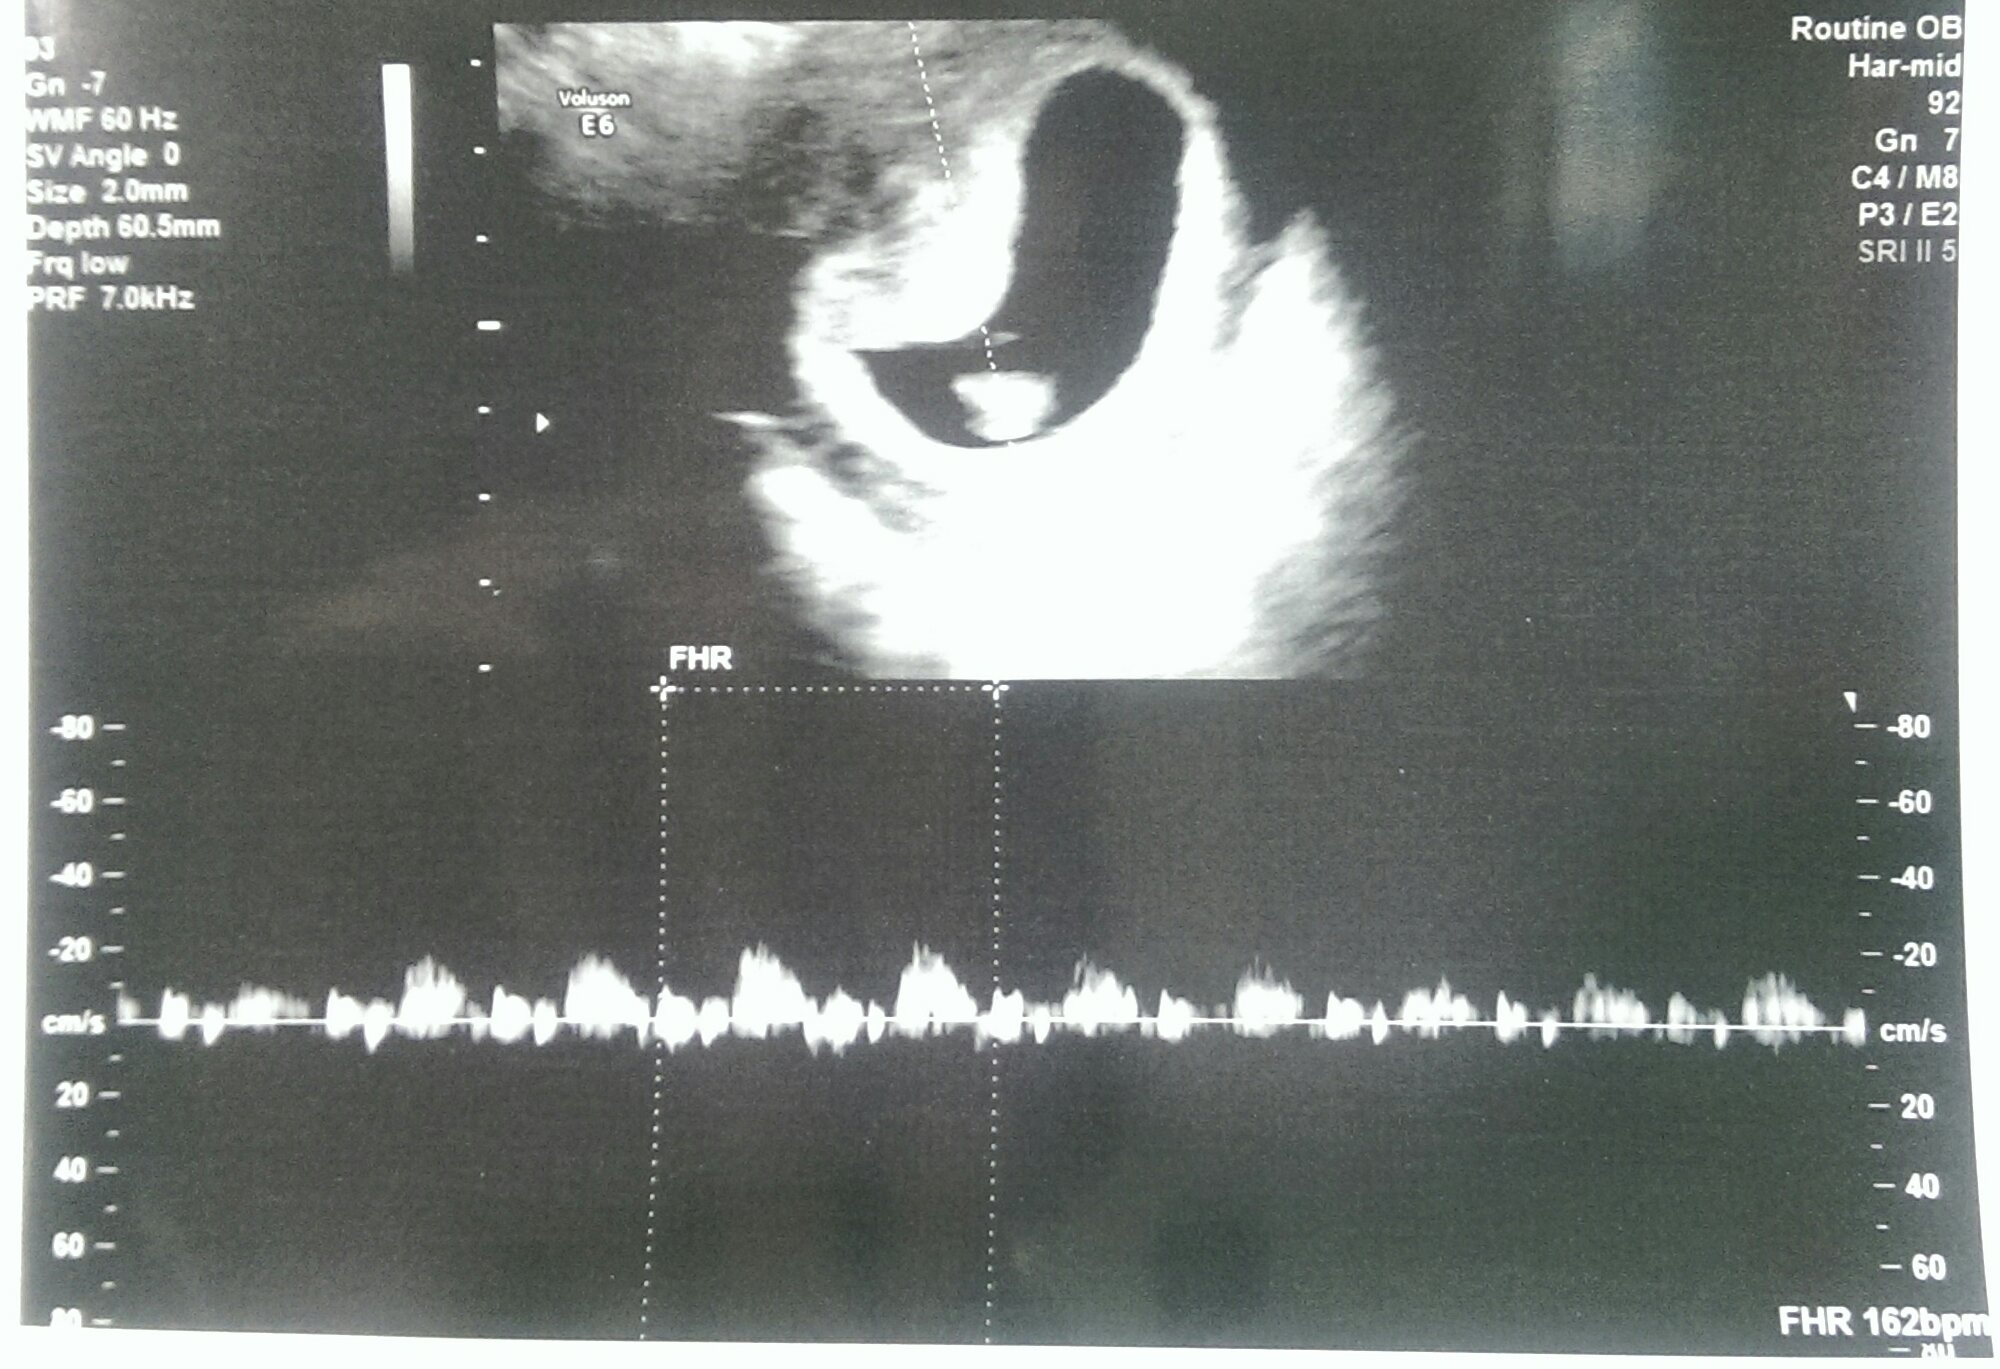

I am due June 5th. Hr was 160